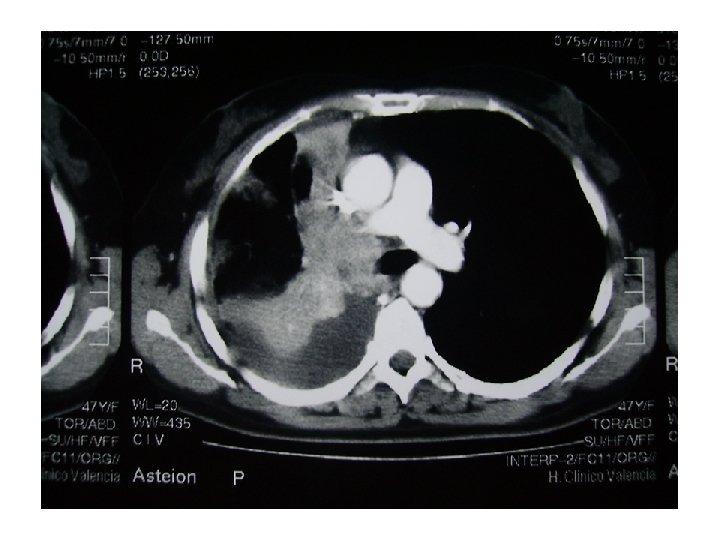

Exploraciones Rx de tórax: ocupación del seno costodiafragmático (¿derrame pleural? ) y masa hiliar derecha con elevación diafragmática homolateral. TAC tóraco-abdominal: gran masa mediastínica hiliar derecha (64 mm x 40 mm); amputación del bronquio principal derecho y afectación de la carina y tráquea en su tercio distal, con ocupación del bronquio lobar superior derecho y colapso completo del lóbulo medio e inferior derecho. La masa infiltra vena cava superior y arteria pulmonar. Se detectan adenopatías subcarinales y paratraqueales superiores e inferiores derechas de 16 a 25 mm, así como infiltrados periféricos en lóbulo superior derecho. En hígado hay tres nódulos hipodensos (segmento II y VI) de 7, 30 y 5 mm respectivamente, de significado incierto. La fibrobroncoscopia objetivó una tumoración que obstruía casi completamente el bronquio intermediario. El estudio histológico fue de adenocarcinoma pobremente diferenciado. El estudio de marcadores genéticos detecta una amplificación (FISS) del EGFr sin mutaciones y una sobre-expresión (en el rango superior de la normalidad) del BRAC 1.